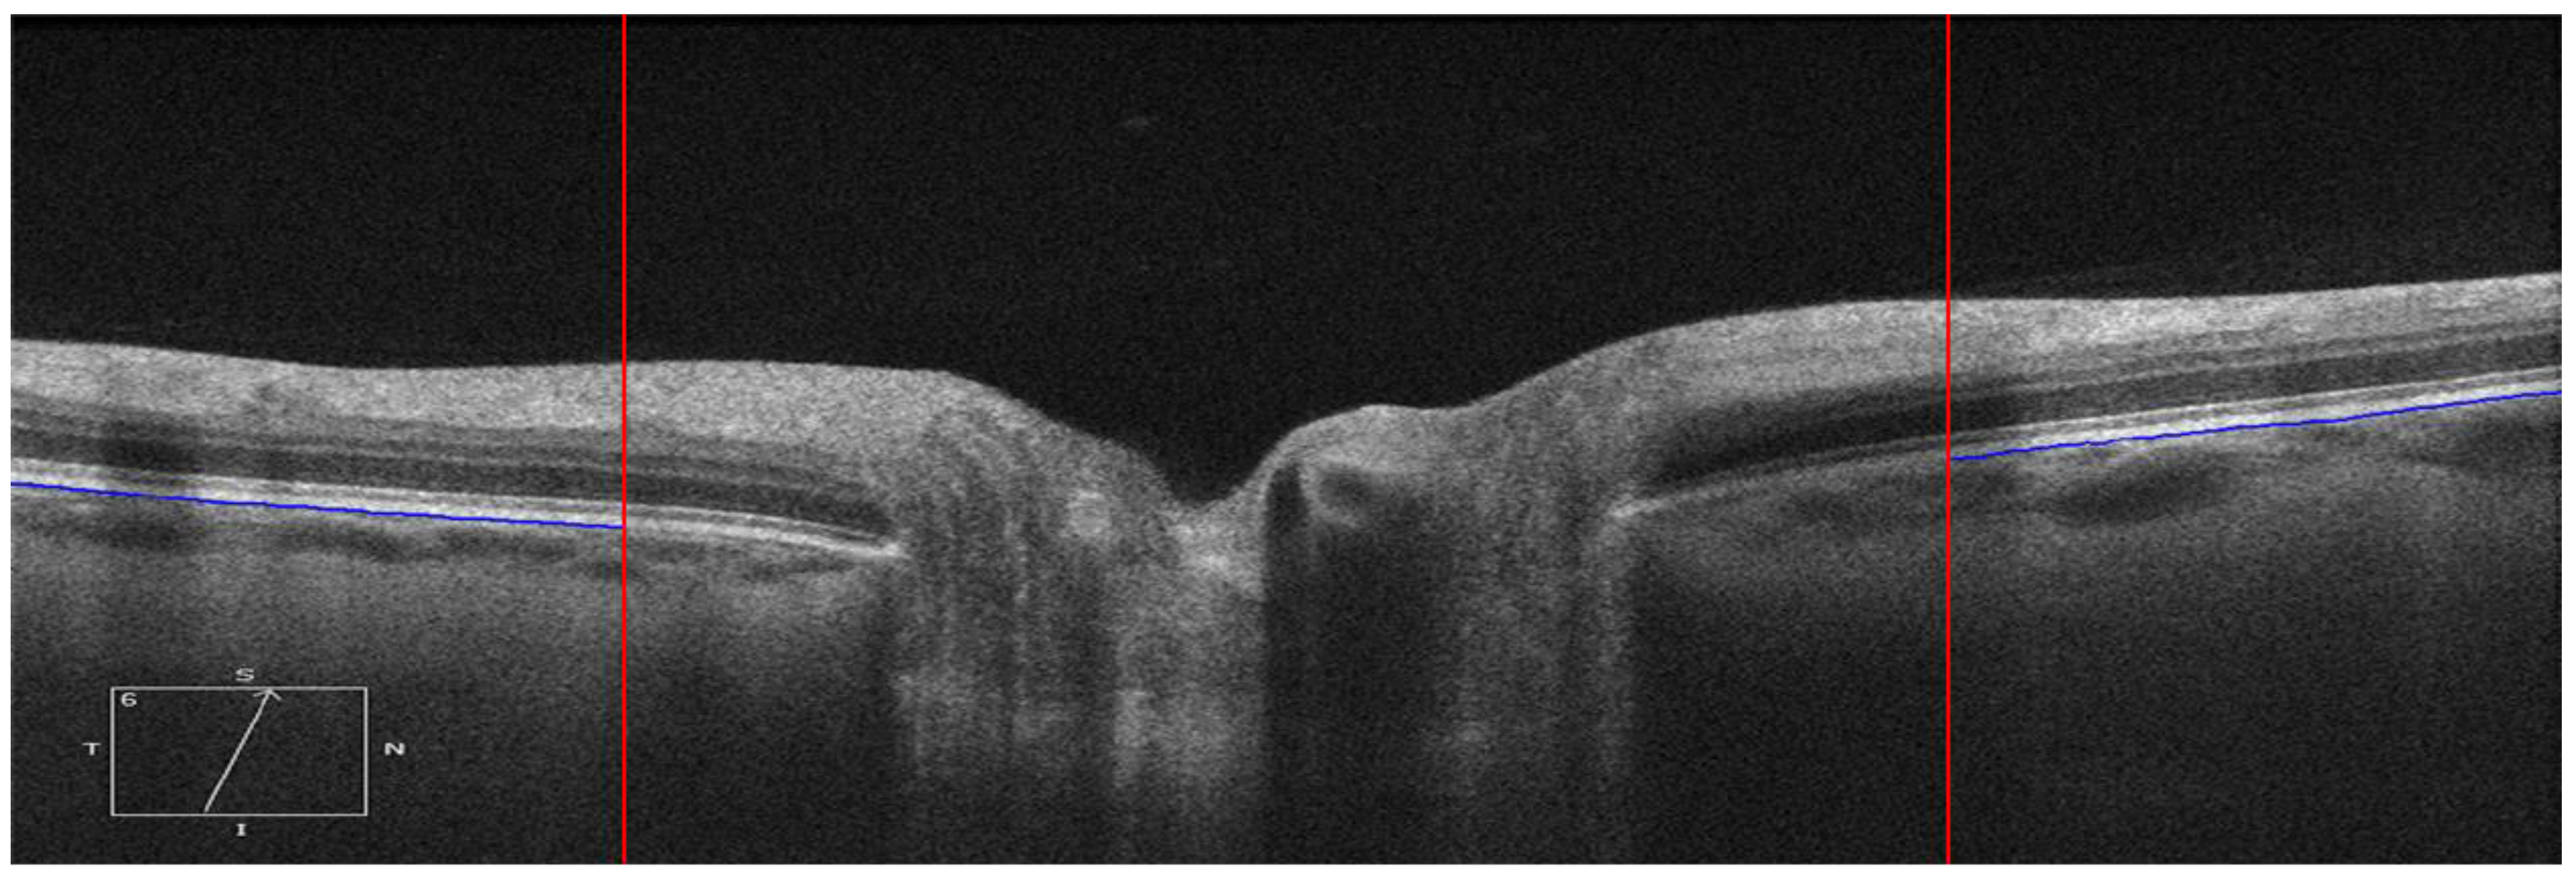

The ppRPE/BM layer in the OCT images was automatically segmented using OCTSEG (Version 0.4, Pattern Recognition Lab, Friedrich-Alexander University) [17]. This open-source segmentation tool has been applied to segment the continuous retinal layers [18,19,20]. However, it was difficult to segment the discontinuous retina layer in the ONH region. Hence, we divided the B-scans into three zones: left, mid, and right with size of 450 × 625 pixel, 976 × 625 pixel, and 450 × 625 pixel, respectively (Figure 2 Top). Both the left and right zones with continuous retina layers were used for the ppRPE/BM layer segmentation. The automatic segmentation results were reviewed by two trained graders independently. If the ppRPE/BM layer was not correctly segmented, manual correction was applied by experienced graders to repaint the segmented layer.

Figure 2. Each B-scan was divided into three zones as marked by two red vertical lines and only the left and right zones were segmented (Top). The segmented ppRPE/BM layers were highlighted in blue color with an angle γ relative to the X-axis. (A,C). The corresponding linear regression models of the segmented ppRPE/BM layers in the left and right zones (B,D).

2.4. Linear Regression of the ppRPE/BM Layer

It should be noticed that the origin of the coordinates is always set at the upper left corner of the scan with X-axis pointing to the right and Y-axis pointing to the inferior. This means that X-axis direction in the left zone is from the periphery to the ONH center, while it is from the ONH center to the periphery in the right zone. The coordinates setting led to a negative slope in the right zone (Figure 2D). To maintain the angle consistency, the angle γ at the right zone was multiplied by −1. In Figure 2B, the slope of the regression line is β = 0.0841, which led to an angle of 4.11°, while in Figure 2D, with β = −0.108, we got the angle of 6.17°.

This tilting artifact can be eliminated by averaging the ppRPE/BM layer angles of the left and right zones from the same cross-sectional B-scan. This averaged ppRPE/BM layer angle was referred to as the cross-sectional ppRPE/BM layer angle and denoted as Γ. A positive Γ indicates a V-shaped ppRPE/BM layer. The angle Γ in Figure 3 was 0.57° before LP, and increased to 1.56° after LP. In addition, this averaging method could also eliminate the artifact induced by the tilting of B-scan relative to the scanning window. Figure 4 illustrates one example in which the OCT scan had a tilt angle of 1.88° against the scanning window. The γ was measured as 4.78° in the left zone and −0.38° in the right zone. The angle Γ was calculated as 2.20°. After we readjusted the scan to its correct position by rotating an angle of 1.88° clockwise, the γ became 6.19° in the left zone and −1.98° in the right zone. The corresponding Γ was calculated as 2.11°, which was only 0.09° less than the one without tilt correction.